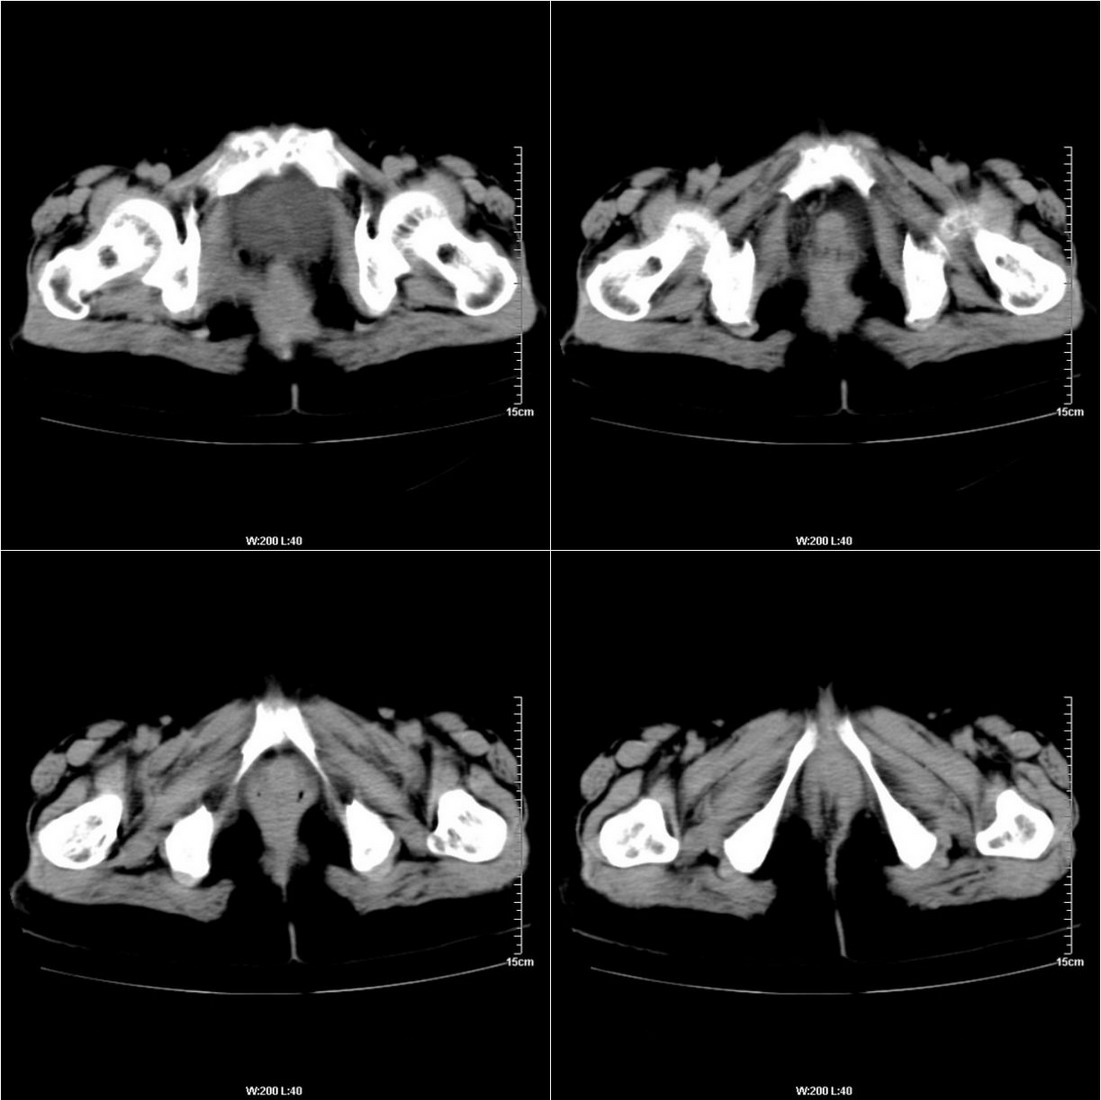

不知道病人的直肠癌手术方式如何,直肠已经全部切除,乙状结肠造瘘于左下腹,肛门应该也没有保留吧?如此,应该是复发了:

病变于肛尾韧带、右侧坐骨肛门窝内并顺右侧肛提肌向右侧闭孔内肌蔓延,骶前软组织内也形成了肿块,麻烦啊!

这个病例还出现了一个有意思的事情:膀胱内在增强的不同时期均有不同形状、位置的高密度出现,并不局限于输尿管开口附近。

是因为尿液中造影剂随输尿管的收缩而排入膀胱内,产生的团片状高密度并进一步弥散而形成的假象吗?渴望哪位老师予以关注并解答,先在此表示感谢了!

膀胱壁见索条状软组织密度影伴强化,可考虑炎性肉芽肿样增生改变,常见于放疗后或慢性感染;直肠及周围软组织见肿块,轻度强化,考虑直肠癌术后复发,并侵犯周围组织